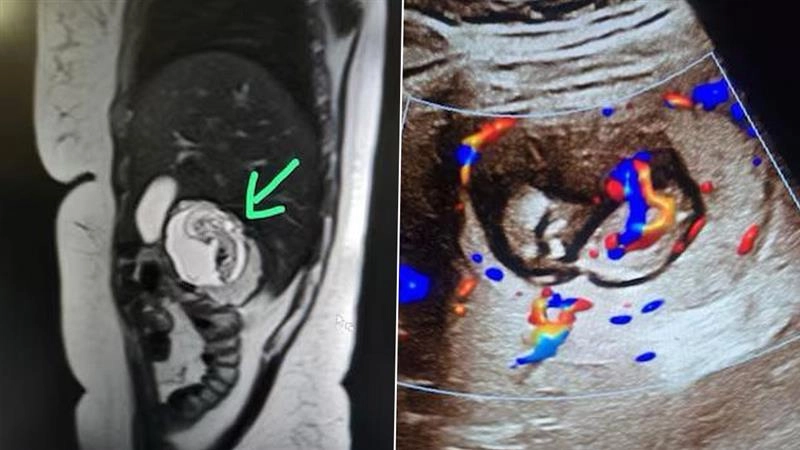

নয়াদিল্লিঃ কয়েক সপ্তাহ ধরেই পেটে অসহ্য ব্যথা,সারাদিন বমি বমিভাব। ইউএসজি (USG) করেও কী রোগ মহিলার তা বুঝে উঠতে পারছিলেন না চিকিৎসকেরা(Doctors)। বাধ্য হয়ে পেটের এমআরআই (MRI) করানোর পরামর্শ দেন চিকিৎসকেরা। এমআরআই রিপোর্টে যা উঠে এল তাতে তাজ্যব চিকিৎসক মহল। জানা গেল, মহিলা গর্ভবতী। কিন্তু জরায়ুতে নয় যকৃতে বেড়ে উঠছে তাঁর ভ্রুণ। অবাক করা ঘটনাটি ঘটেছে উত্তরপ্রদেশের মিরাটে। চিকিৎসকেরা জানিয়েছেন ৩০ বছরের ওই মহিলার লিভারের ডান প্রকোষ্ঠের ভিতরে প্যারেনকাইমাল টিস্যুর গভীরে রয়েছে ভ্রুণটি। তাঁর জরায়ু সম্পূর্ণ খালি রয়েছে। পরীক্ষা করে দেখা গিয়েছে ভ্রুণের হৃদস্পন্দন স্বাভাবিক রয়েছে।

জানা গিয়েছে, চিকিৎসাবিজ্ঞানের ভাষায় এই গর্ভাবস্থাকে ইন্ট্রাহেপ্যাটিক এক্টোপিক প্রেগন্যান্সি বলে। এটি অত্যন্ত বিরল গর্ভাবস্থা। পৃথিবীর ইতিহাসে এখনও পর্যন্ত এই ধরনের ৮ টি কেস পাওয়া গিয়েছে। সম্ভবত ভারতের প্রথম ইন্ট্রাহেপ্যাটিক এক্টোপিক প্রেগন্যান্সির ঘটনা এটি। এই গর্ভাবস্থা বিপজ্জনকও বটে। কারণ লিভারের মধ্যে প্রচুর রক্তনালী থাকে যেখানে রক্ত সরবরাহ হয়। লিভারের মধ্যে ভ্রুণ বড় হতে থাকলে রক্তনালির চাপে লিভার ফেটে যেতে পারে। অস্ত্রোপচার করে ভ্রূণটি অপসারণ করানো যেতে পারে। কিন্তু তা অত্যন্ত ঝুঁকিপূর্ণ।